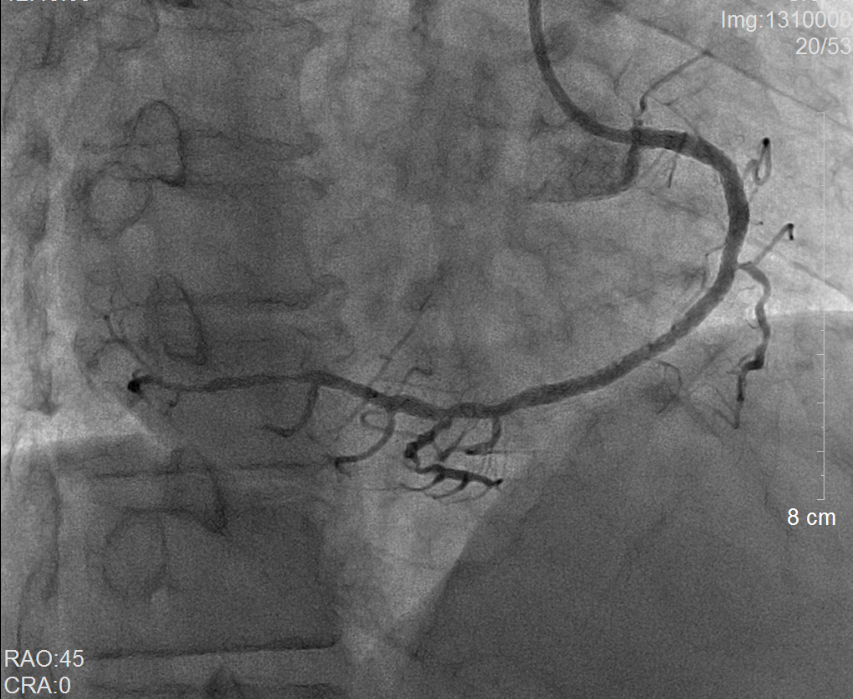

術前冠脈造影提示右冠狀動脈彌漫性病變                 術后冠脈造影提示右冠狀動脈血流通暢

當地縣醫院立即通過胸痛中心急救系統向我院心內科發出求助。當日二線值班的副主任醫師謝泓及住院總醫師李愛娜了解情況后當即決定將患者轉入我院,備行急診經皮冠狀動脈介入治療(PCI)。而值急診介入班的彭峰副主任醫師和蔡瀚醫師得知消息后也立即趕往待命。風馳電掣的120急救車一到達醫院后,接診醫生立即將林先生送往介入手術室。不料,術中冠脈造影提示林先生為極其罕見的“右位心合并急性心肌梗死”,這無疑大大增加了手術的操作難度。憑借心內科介入組醫護人員平日的訓練有素和嫻熟配合,很快就為林先生開通了“犯罪血管”——右冠狀動脈,從進入醫院大門至球囊打通血管的時間(D-to-B)僅僅60分鐘(國際標準為<90分鐘)。